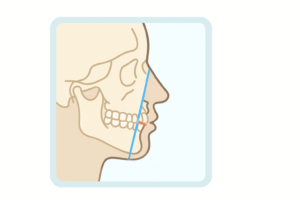

骨格のバランス(上下顎の位置関係)

顔の縦方向(開咬傾向/過蓋咬合傾向など)

下顎の回転(時計回り・反時計回り)と治療目標の設定

前歯の傾き(上顎前歯・下顎前歯)

上下の前歯の位置関係(オーバージェット/オーバーバイトの背景)

軟組織(口元・唇の位置)の評価

抜歯/非抜歯の検討材料(口元・前歯の突出感・スペース不足の整理)

「抜歯が必要ですか?」は多くの方が調べるテーマです。

セファロは、歯並びのスペース不足だけでなく、口元の印象・前歯の位置・骨格を含めて、抜歯/非抜歯の合理性を検討する材料になります。